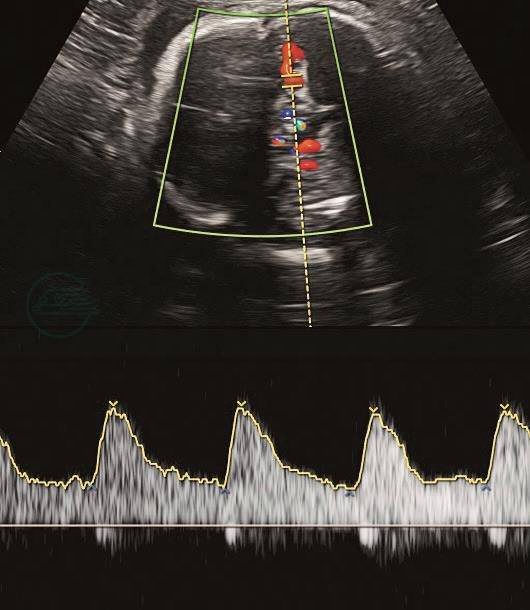

(2)大脑中动脉:胎儿宫内慢性缺氧时,由于脑保护效应,出现舒张期血流增加,PI降低(图3)。

图3大脑中动脉

妊娠34+5周,大脑中动脉舒张期血流增加